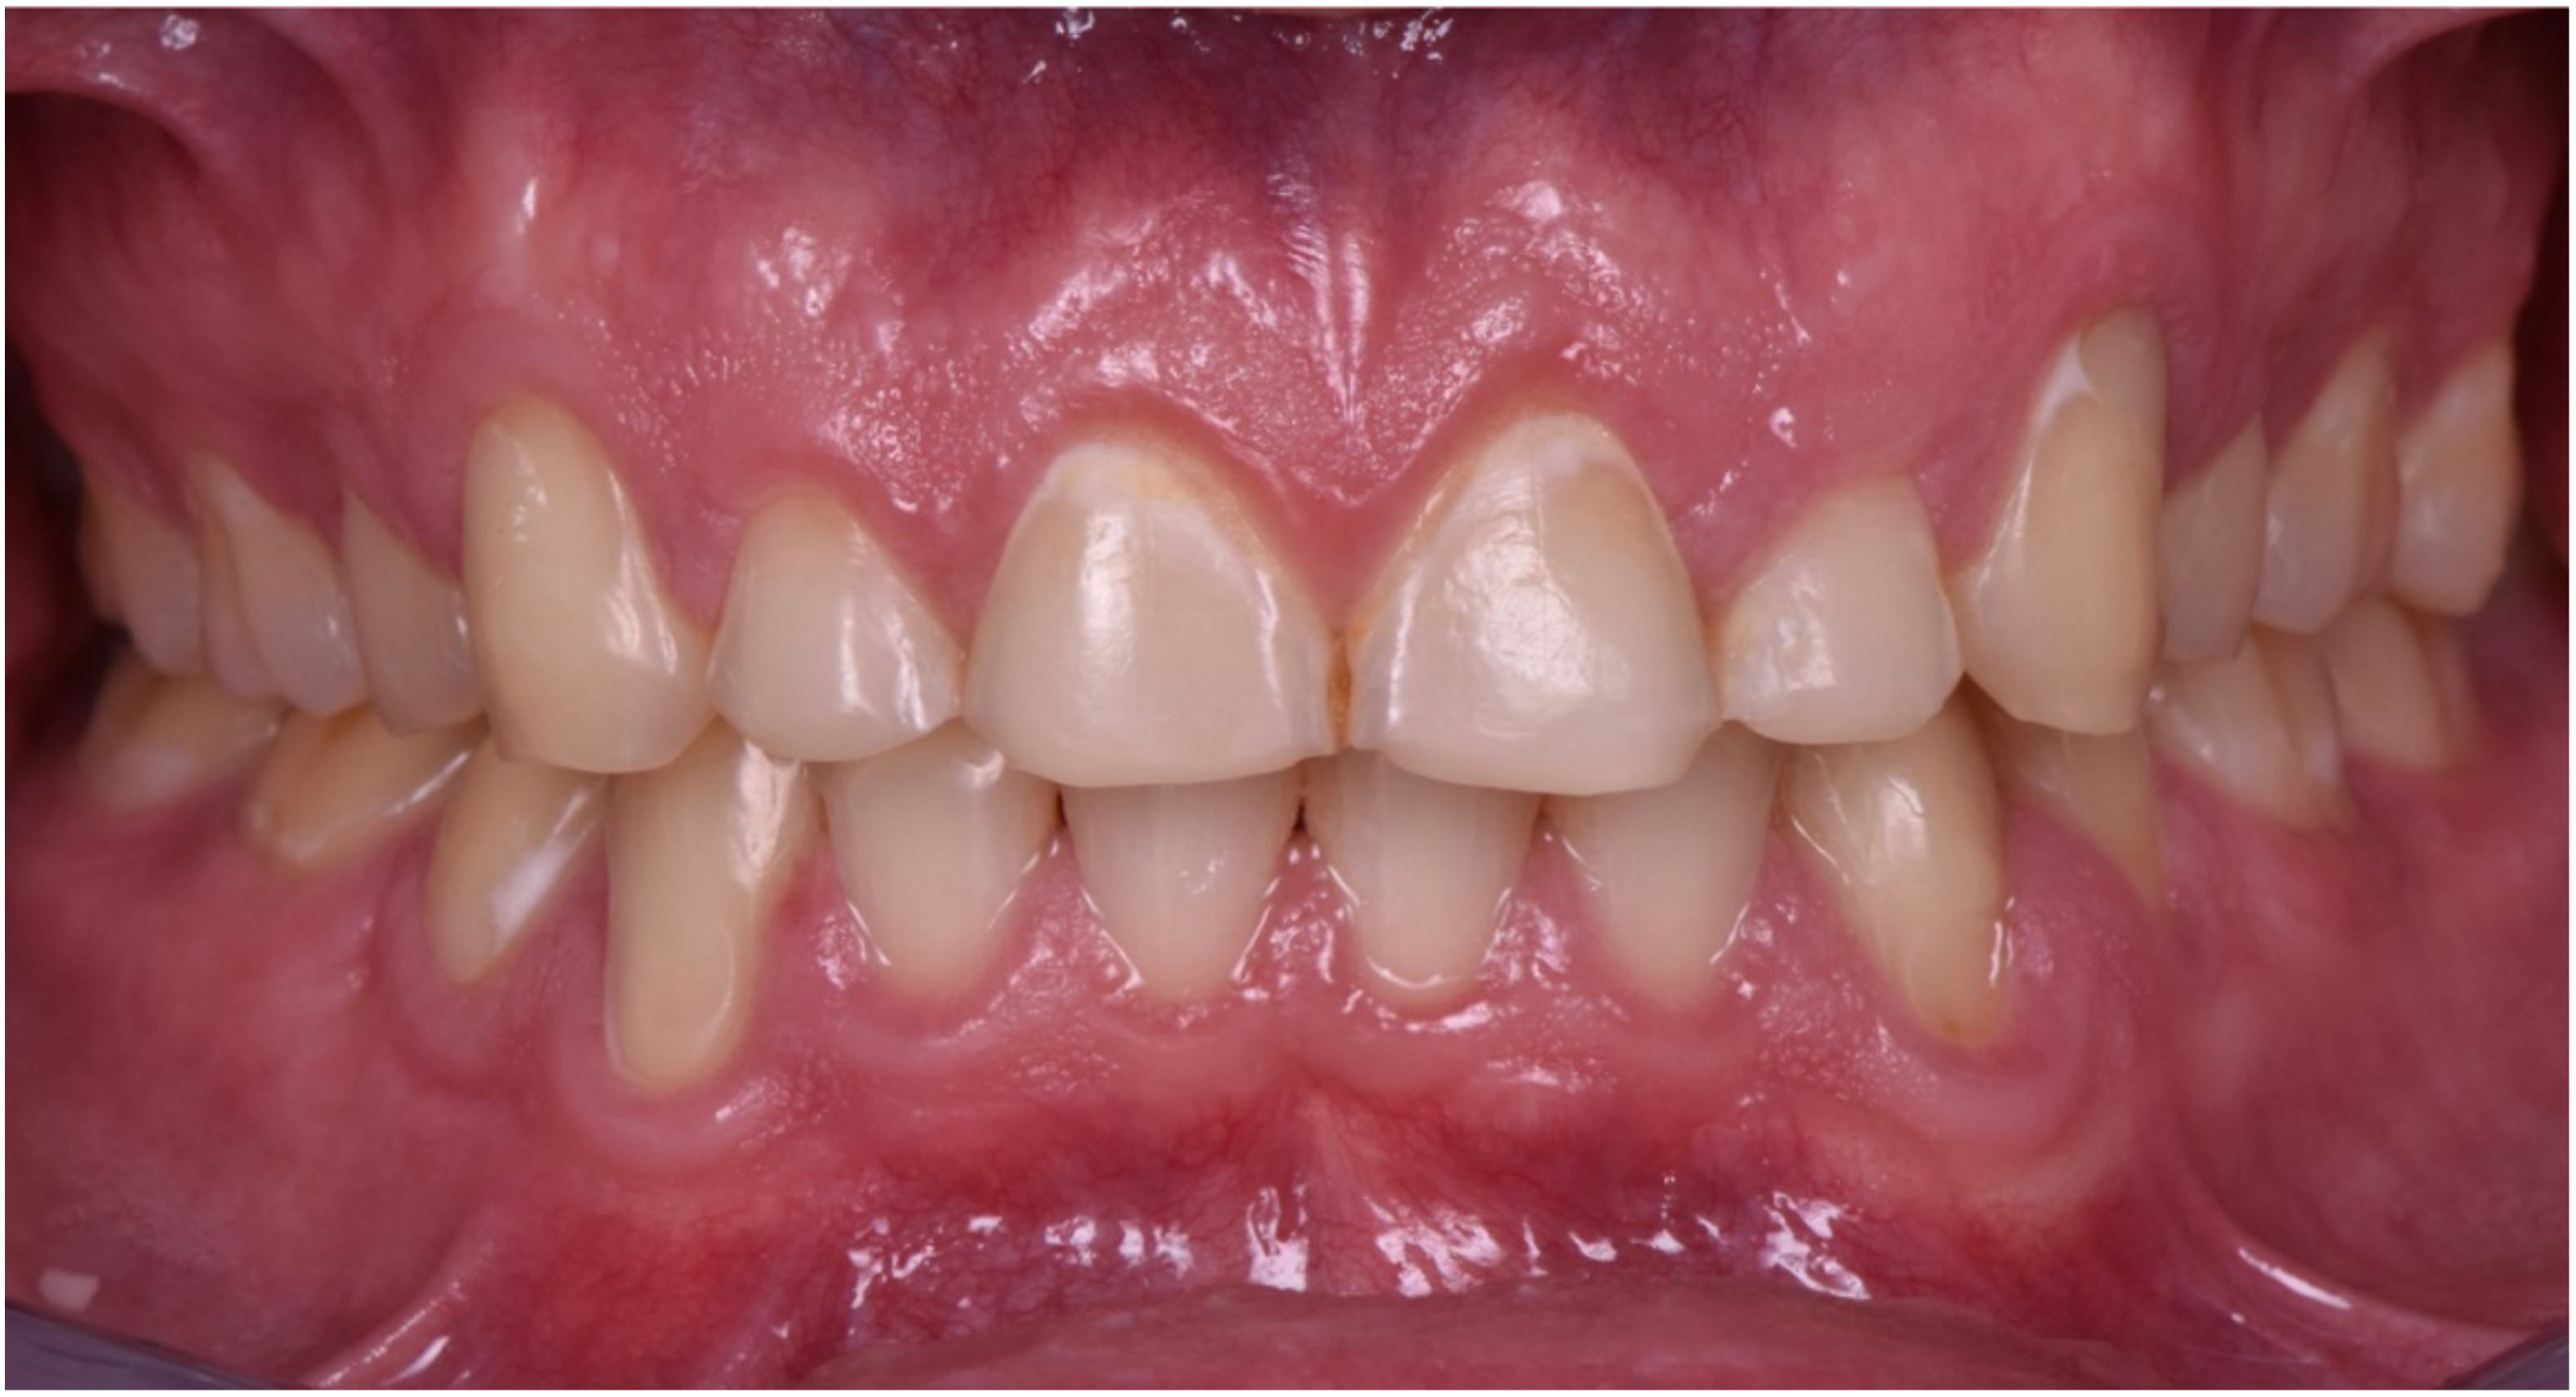

2. Clinical Report